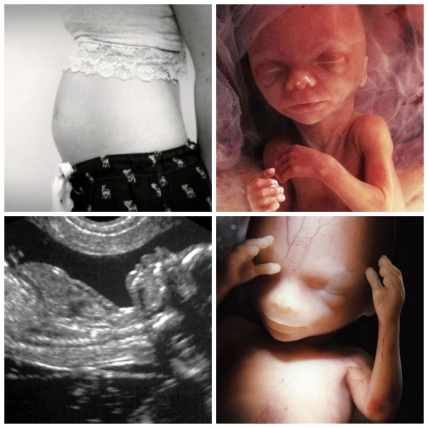

БУДУЩИЙ МАЛЫШ НА 14 НЕДЕЛЕ БЕРЕМЕННОСТИ

На 14 неделе будущий малыш по размерам как среднее яблоко: его вес около 30-35 г., а рост 10-11 см. и он продолжает активно расти. Кроха уже достаточно похож на новорожденного: его лицо становится выразительнее с каждым днем, вполне различимы уши, щеки, носик, глаза сдвигаются к переносице, но все еще прикрыты веками, есть реснички и брови, развита мимика.

Все более чувствительным становится кожный покров, развиваются вкусовые рецепторы малыша, продолжается формирование костного скелета из хрящевого, потихоньку развиваются ребра. С помощью диафрагмы малыш тренируется делать дыхательные движения.

С наступлением 14 недели беременности у ребёнка формируются половые органы, однако узнать пол будущего малыша на этом периоде еще вряд ли удастся.

На 14 неделе продолжается формирование на коже малыша лануго – тоненького пушка из волос, зеркально повторяющих рисунок кожи. Живет и функционирует каждый маленький волосок не долго, на смену одному, достаточно быстро выпавшему, вырастает другой. Выпавшие волоски попадают в околоплодные воды. Основная функция лануго – защитная, этот волосяной пушок задерживает восковидное вещество, которое выделяет детский организм, образуя плотную смазку. Смазка необходима ребенку чтобы во время родов максимально легко проходить по родовым путям.

: «Хрящи, составляющие скелет ребенка, превращаются в кости. Руки достигают длины, пропорциональной телу, но ноги еще отстают. Гениталии можно характеризовать как мужские и женские, но на УЗД они еще не различимы. Ребенок может зевать и даже сосать палец, он кувыркается, но пока вы этого не чувствуете. Организм плода начинает выделять мочу в околоплодные воды. Длина ребенка 8,7 см, как груша, вес 45 г.»

Оценка составляется на основании таких параметров как диаметр живота и грудной клетки плода, длина бедра, а также бипариетальный размер. Бипариетальный размер–фактическое расстояние между противоположными стенками (наружными контурами) теменных костей черепа. Этахарактеристикаразмеров головыбудущего малыша важна для оценки возможности прохождения по родовым путям.Также именно увеличение размера черепной коробки является признаком развития головного мозга и может своими размерами указывать, нормально ли идет его развитие.

Также на 14 неделе беременности на УЗИ можно оценить развитие костей малыша: локтей, плеч, лучевых костей, малоберцовых и большеберцовых, стоп и кистей рук, дать оценку работе внутренних органов, таких как сердце, почки, желудок, мочевой пузырь и кишечник.